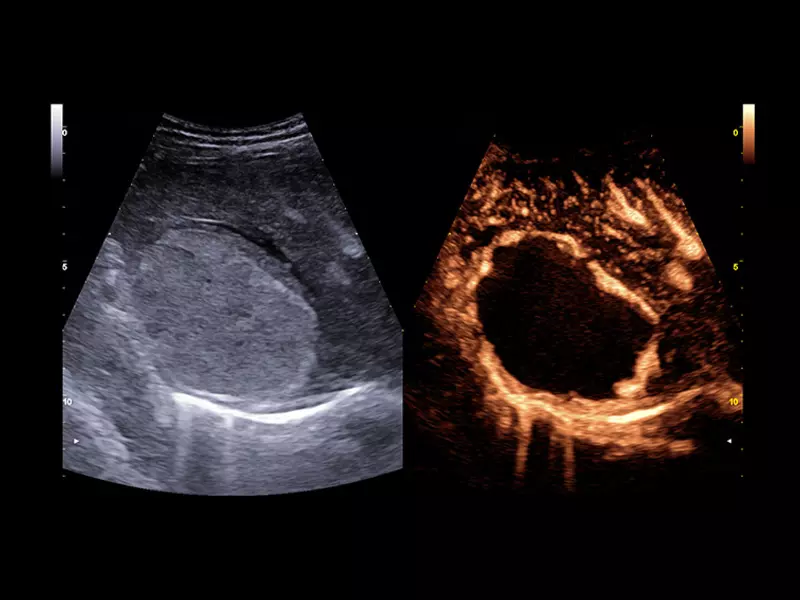

MyLab™9 Platform - High resolution imaging in testis

MyLab™9 Platform - High resolution imaging in testis